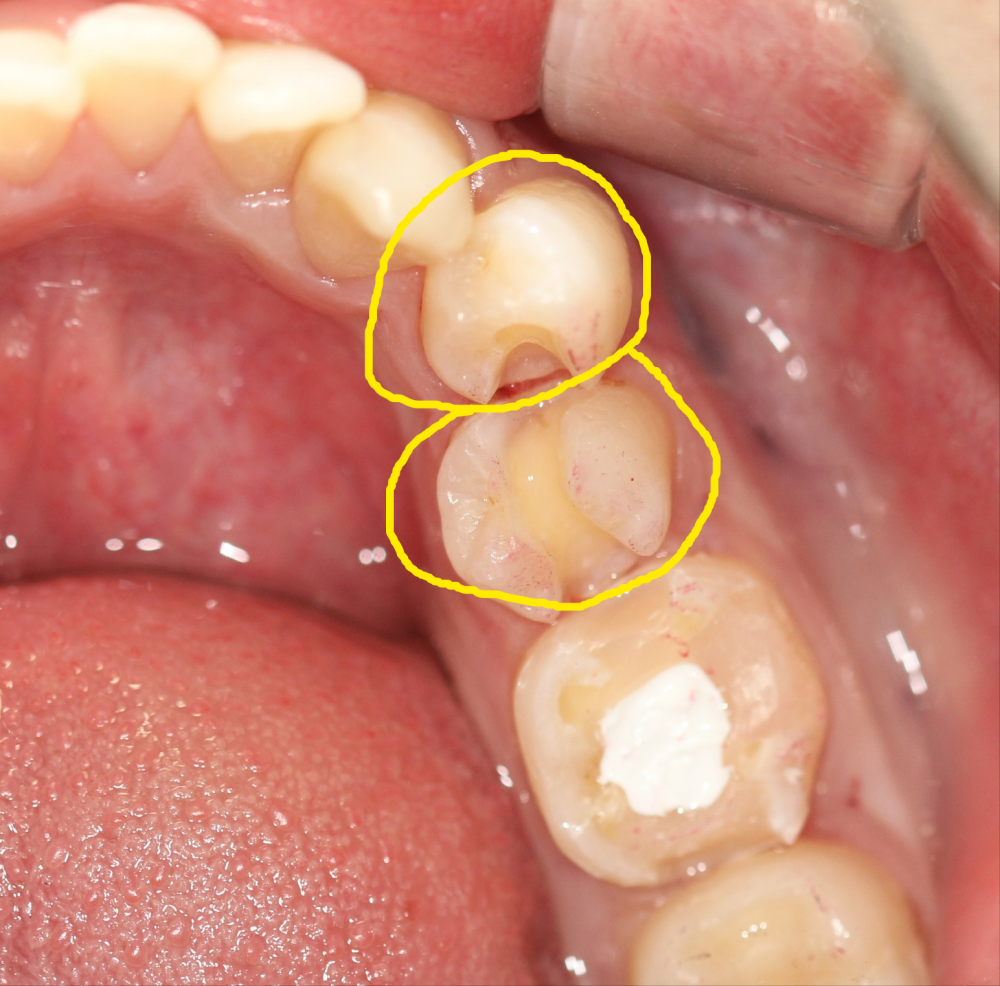

퀴즈! 이맥스 인레이치료한 치아를 찾아주세요

힌트 : 2개

답: 작은어금니 2개

이맥스는 심미적 장점, 치아와 비슷한 강도, 뛰어난 접착력 흠잡을데 없는 재료입니다.